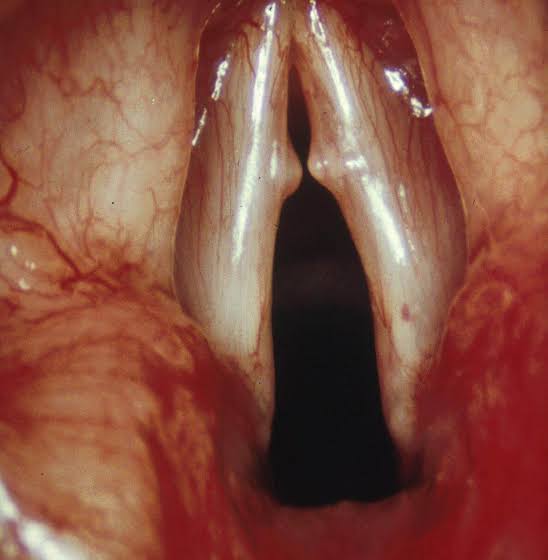

Everyone, and I mean everyone, has a vocal break; a point where your voice might crack or break as you try to sing higher. In truth, it's just a point where your voice wants to shifts gears. For most male singers, this break usually happens around E4, just above middle C. For female singers, the break typically occurs around A4, just below tenor C.